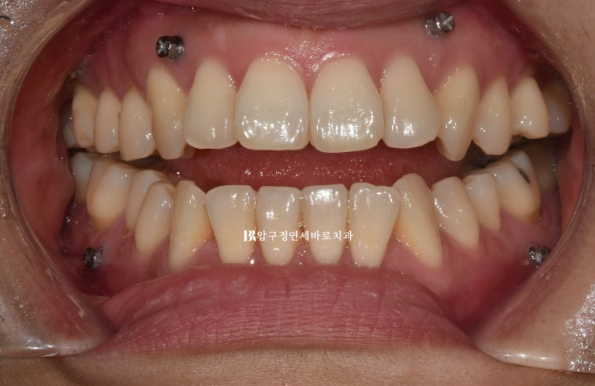

선수술로 양악수술을 한 뒤에 한달 후 내원했을 때의 사진입니다.

23.02

심한 개방교합이 관찰되는 환자분입니다.

수술이 잘못된걸까요?

아닙니다. 물리치료를 하는 기간이라 그렇습니다.

잇몸에 심어진 나사에 고무줄을 걸며 턱 위치를 안정화 시키는 과정이 필요합니다.

IVRO인지 SSRO인지 수술방법에 따라 그리고 수술결과에 따라 이 과정이 몇 달 걸릴 수 있습니다.

턱 위치가 안정이 된 후 교정을 시작하기로 하고 물리치료도 몇 달 더 진행했습니다.